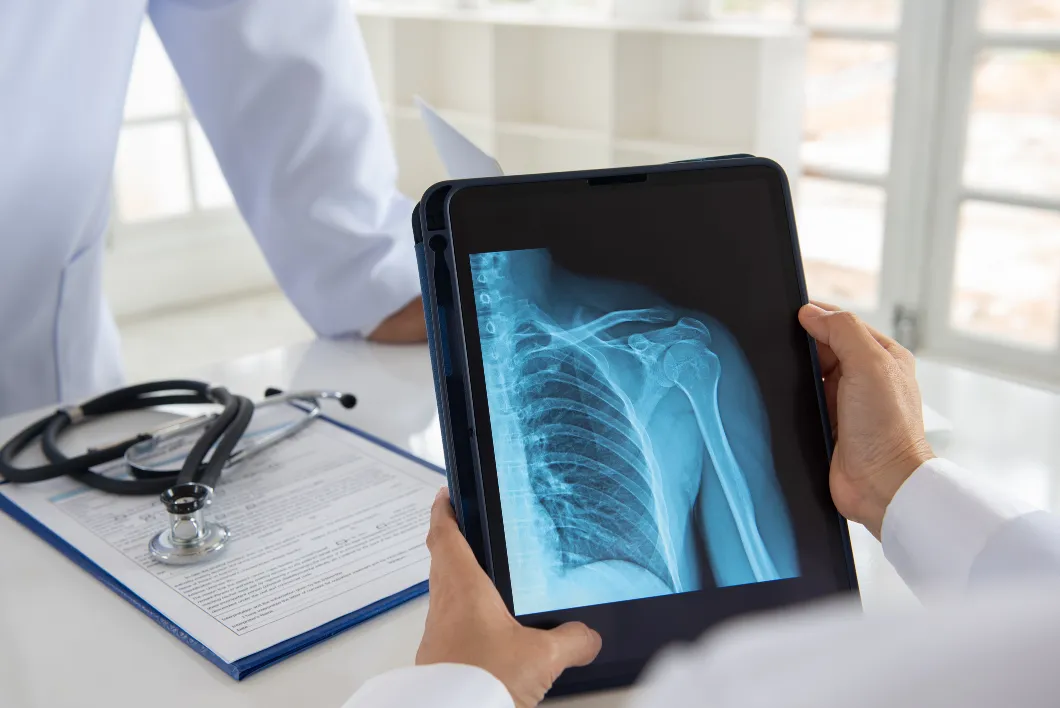

Regardless of the duration of shoulder pain symptoms or the type of pain experienced, locating the cause of the problem is essential to receiving proper treatment. Like many other conditions, shoulder pain is diagnosed with a series of tests, including active ranges of motion, orthopedics, and muscle strength.

For the most complete diagnosis of shoulder pain, an x-ray and even an MRI can also be important. While x-rays are best for viewing joint deterioration and alignment of the shoulder, MRI is the best imaging for diagnosis of muscular, ligamentous damage, or torn rotator cuff. Sometimes MRI can complicate the diagnosis process, as previous injuries can sometimes show positive findings – even if they are not contributing to the current shoulder pain.